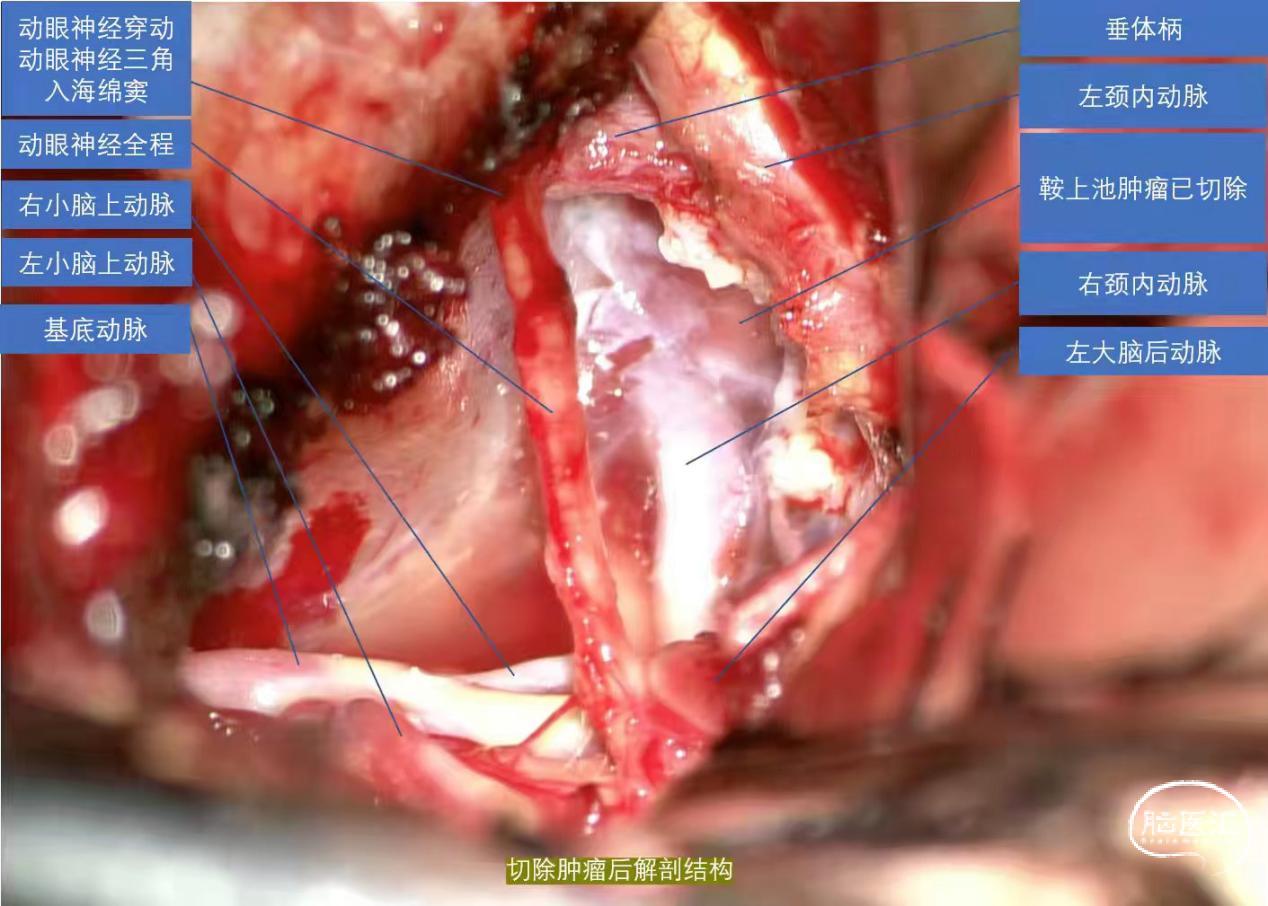

经科室讨论后决定行左侧颞下岩前入路颅底病损切除术。

手术顺利,患者目前恢复良好,病情平稳,未诉疼痛。

该患者肿瘤分布于桥小脑角、脚间池、鞍上池,分布范围广、手术难度大。